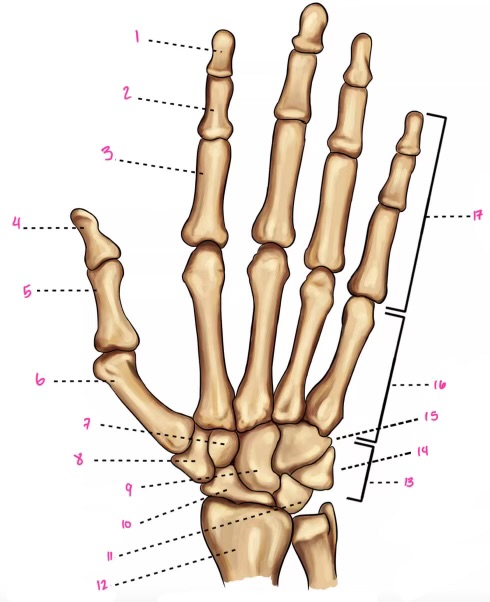

1

1

2

2

3

3

4

9

5

10

6

11

7

14

8

15

9

16

10

17

11

18

12

1

13

2

14

3

15

4

16

5

17

6

18

7

19

8

20

9

7

22

8

23

9

24

10

25

11

26

13

27

14

28

15

29

16

30

17

Phalanxes